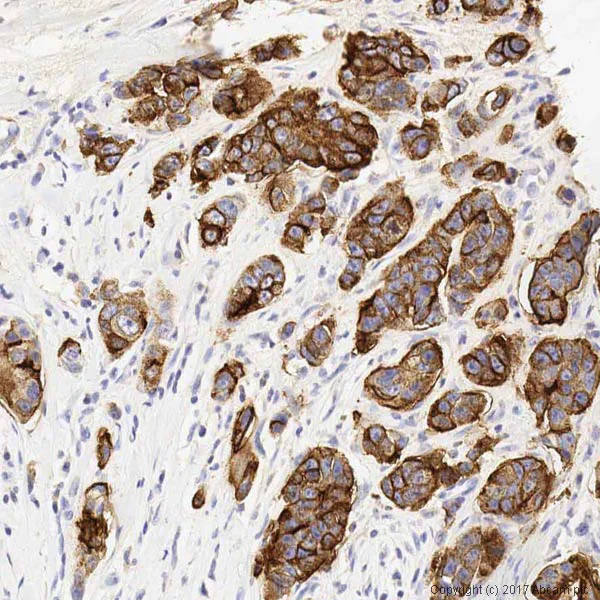

Immunohistochemistry (Formalin/PFA-fixed paraffin-embedded sections) - Anti-MUC1 antibody [SM3] - BSA and Azide free (AB230294)

IHC image of MUC1 staining in a formalin fixed, paraffin embedded human breast carcinoma tissue section*, performed on a Leica Bond™ system using the standard protocol F. The section was pre-treated using heat mediated antigen retrieval with sodium citrate buffer (pH6, epitope retrieval solution 1) for 20 mins. The section was then incubated with ab22711, 10 μg/ml, for 15 mins at room temperature and detected using an HRP conjugated compact polymer system. DAB was used as the chromogen. The section was then counterstained with hematoxylin and mounted with DPX.

This data was developed using the same antibody clone in a different formulation containing PBS and azide (ab22711).